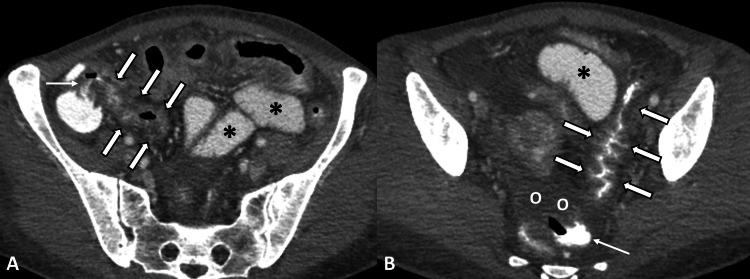

Cocaine represents one of the most frequently used recreational drugs worldwide. Cocaine-related disorders mostly affect the nervous and cardiovascular system, although gastrointestinal complications are not negligible and sometimes life-threatening. The most common gastrointestinal manifestations of cocaine abuse are ulceration, infarction, perforation, ischemic enterocolitis, and rarely hemorrhage, with mesenteric ischemia being the underlying pathophysiological mechanism. Herein, we report a rare case of cocaine-induced small bowel obstruction in a young female patient, caused by chronic mesenteric ischemia and excessive intestinal wall fibrosis.

可卡因是全球最常用的消遣性毒品之一。与可卡因相关的疾病主要影响神经和心血管系统,尽管胃肠道并发症也不容忽视,有时甚至会危及生命。可卡因滥用最常见的胃肠道表现是溃疡、梗死、穿孔、缺血性小肠结肠炎,很少有出血情况,肠系膜缺血是潜在的病理生理机制。在此,我们报告一例年轻女性患者罕见的可卡因诱发的小肠梗阻病例,其病因是慢性肠系膜缺血和肠壁过度纤维化。